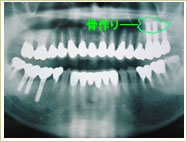

●骨作りを行った症例

38歳 女性 インプラント埋入数:6本 画像拡大

治療前

治療前   治療前

骨作り

骨作り 骨作り